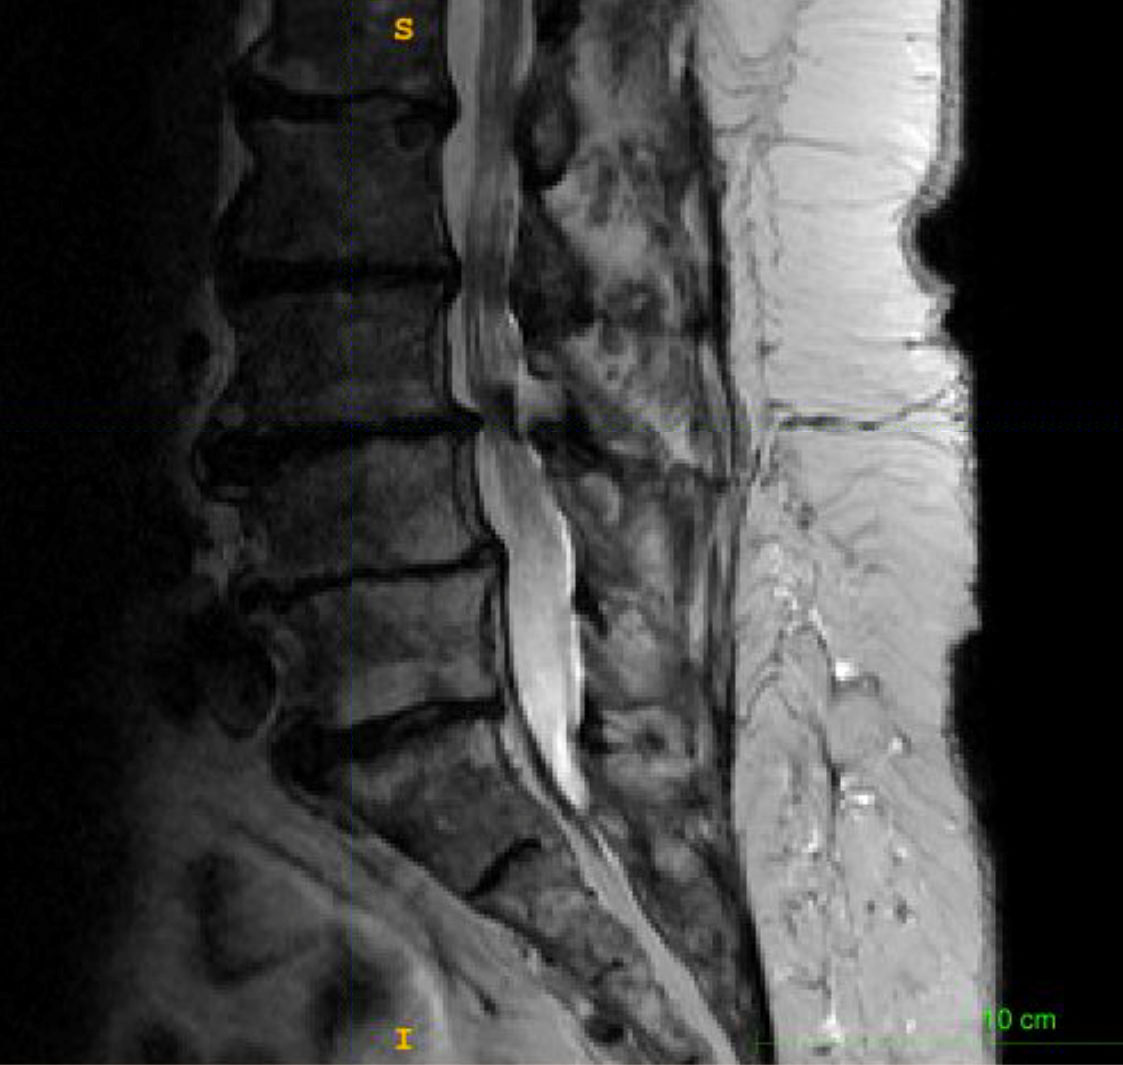

Maximum Disc Height

height: 6.5 mm

percentile: 6.8 %

relative: 55.6 %

height: 3.8 mm

percentile: 0.0 %

relative: 32.5 %

Cohort statistics:

• female

• 57 - 67 years

• 1500 patients